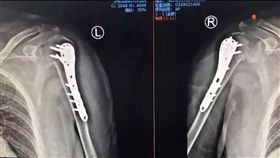

僅「愛的抱抱」 妻竟雙肩粉碎性骨折

怎麼會這樣?只是一個「愛的抱抱」,竟搞到雙肩粉碎性骨...